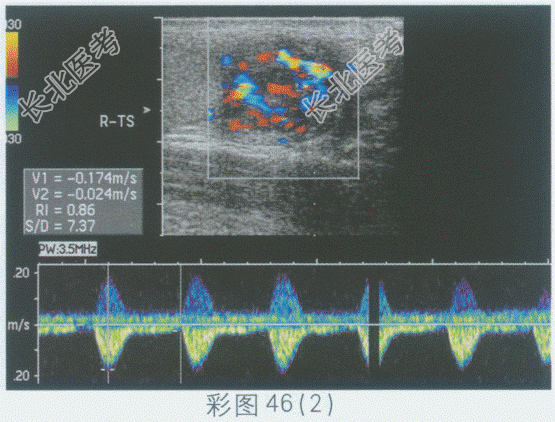

超声综合描述:右侧睾丸形态、大小正常, 内回声均匀。右侧附睾尾回声减低,范围: 4.1cm×4.3cm,内回声不均, CDFI:内可见丰富动静脉血流信号, PW:以动脉频谱为主, V

17.0cm/s。见下图及彩图46。